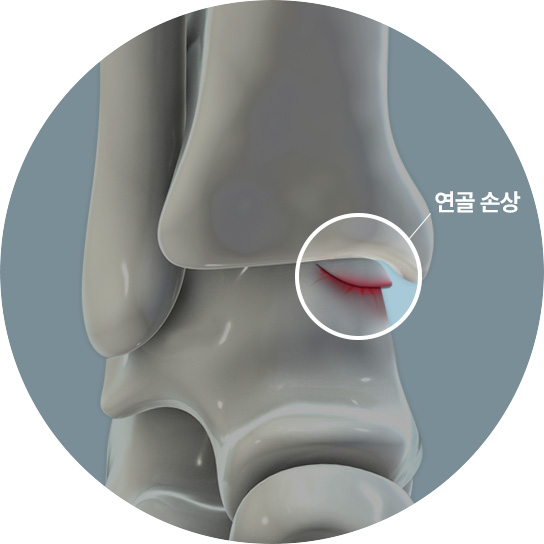

발목 연골은 발목 뼈의 끝부분을 덮고 있는 매끄럽고 탄력적인 조직으로, 뼈와 뼈 사이의 마찰을 줄여

부드러운 움직임을 가능하게 하고 충격을 흡수하는 역할을 합니다.

걷거나 뛰는 등의 활동 시 발목 관절에 가해지는 충격을 완화시켜 주고, 관절의 안정성을 유지하는 데 중요한 역할을 합니다.

다양한 원인으로 인해 발목 관절의 연골이 손상되는 것을 말합니다.

손상 정도는 얕은 균열부터 깊은 파열,

연골 조각이 떨어져 나가는 경우까지 다양합니다.